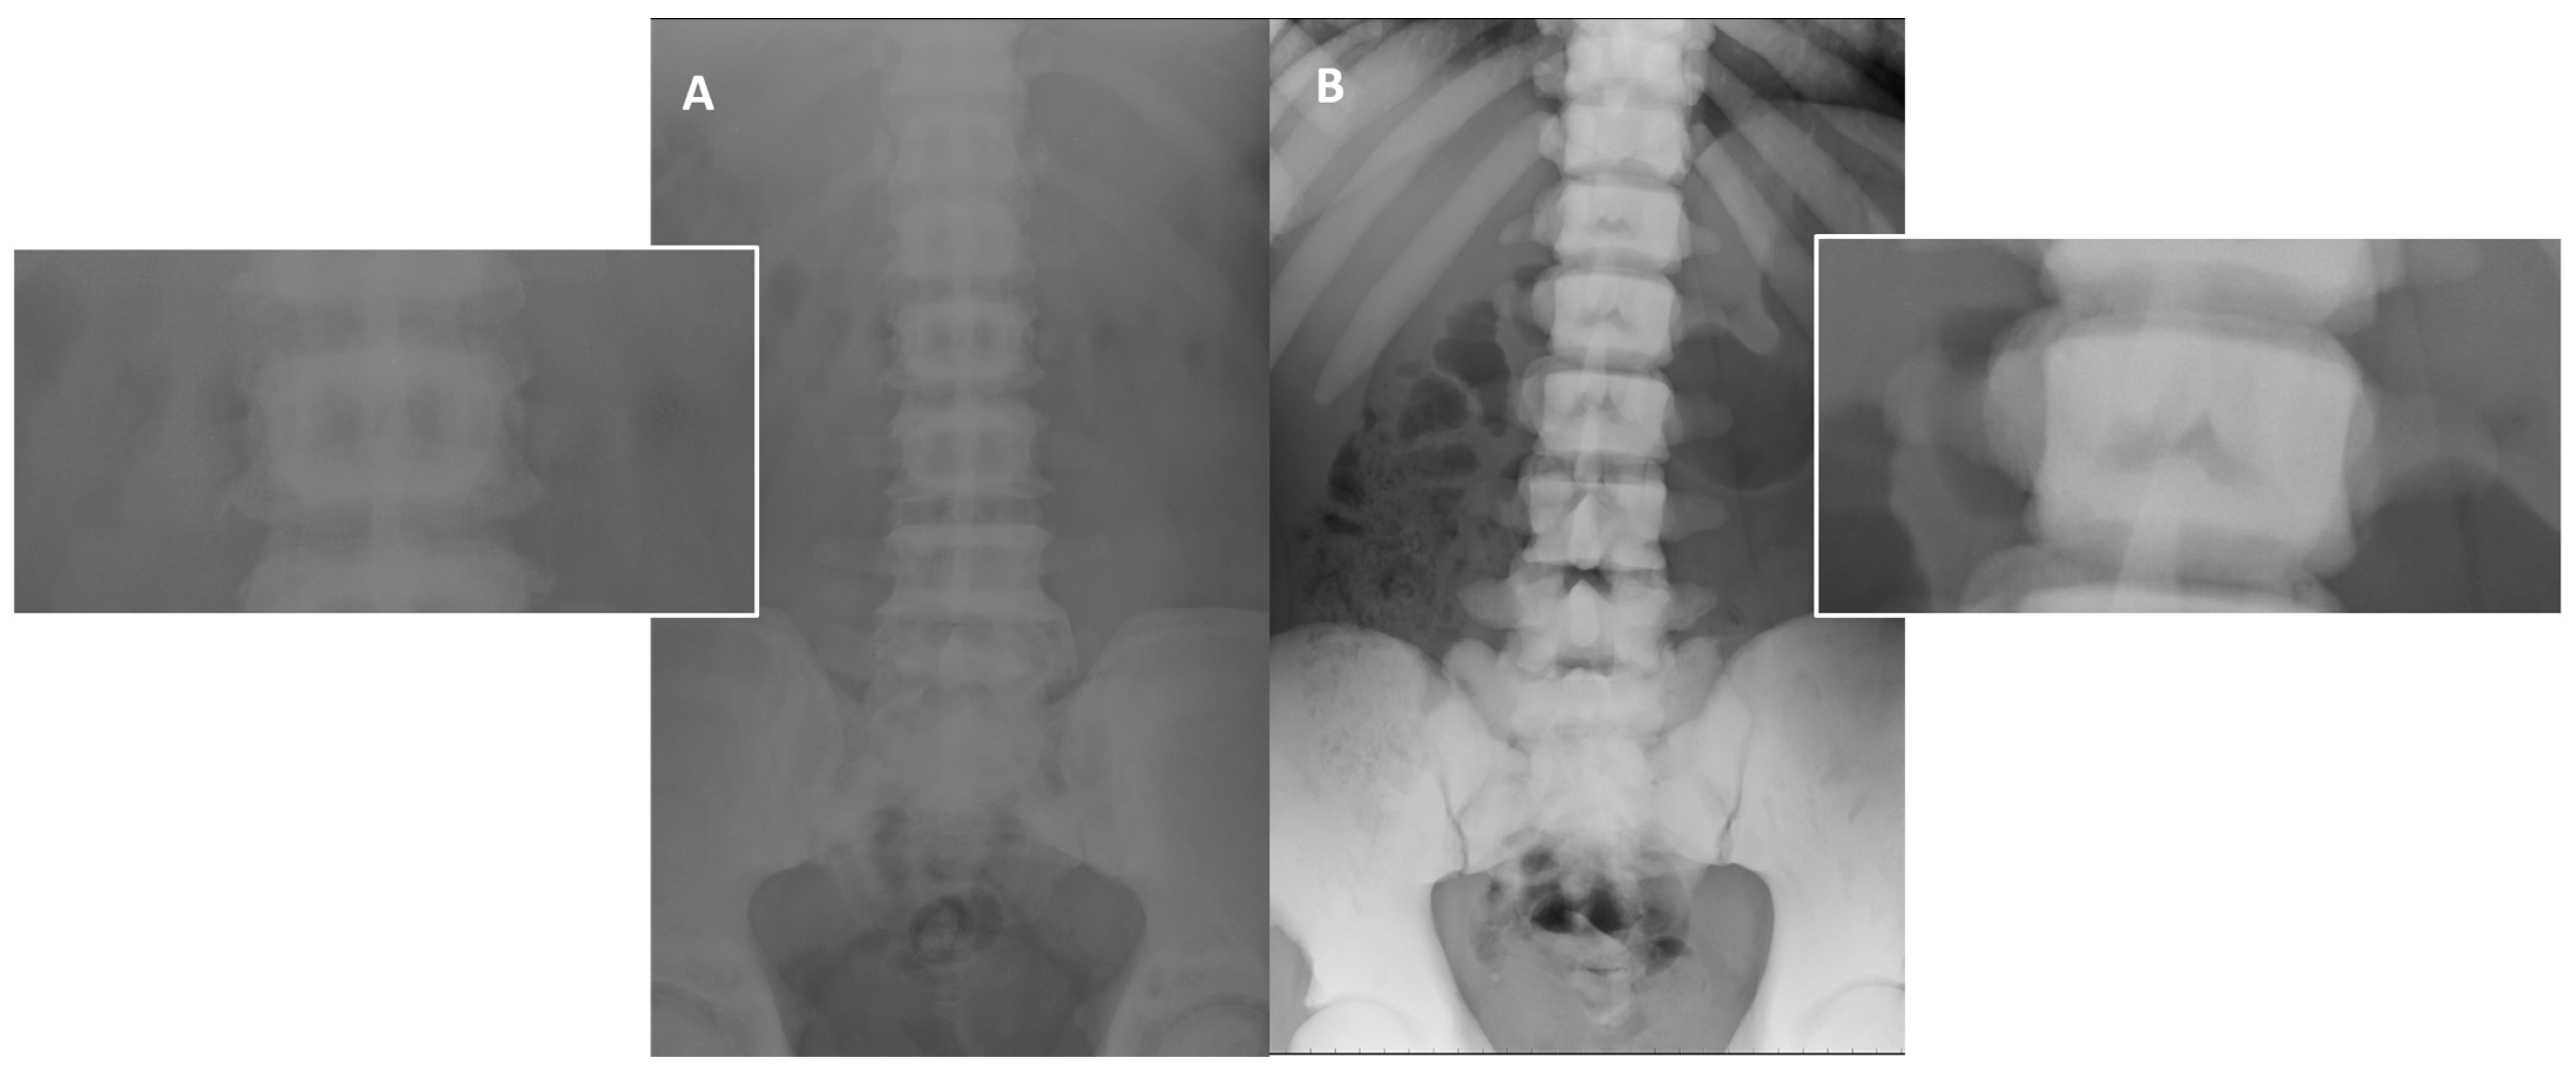

It is well known that the different genetic patterns of osteopetrosis reflect in different clinical manifestations, prognosis, age of symptoms onset, and nonetheless different radiological features (Figure 8).

Figure 8. Different pattern of bone sclerosis in different type of osteopetrosis. Conventional radiographies (AP projection) in osteopetrosis ADO type 2 (A) and ARO (B) show different type of abnormally increased bone density: well-defined sclerosis of vertebral endplate (‘rugger jersey spine’—(A)) in ADO type 2, and complete and marked sclerosis of the whole vertebrae in ARO type (B).